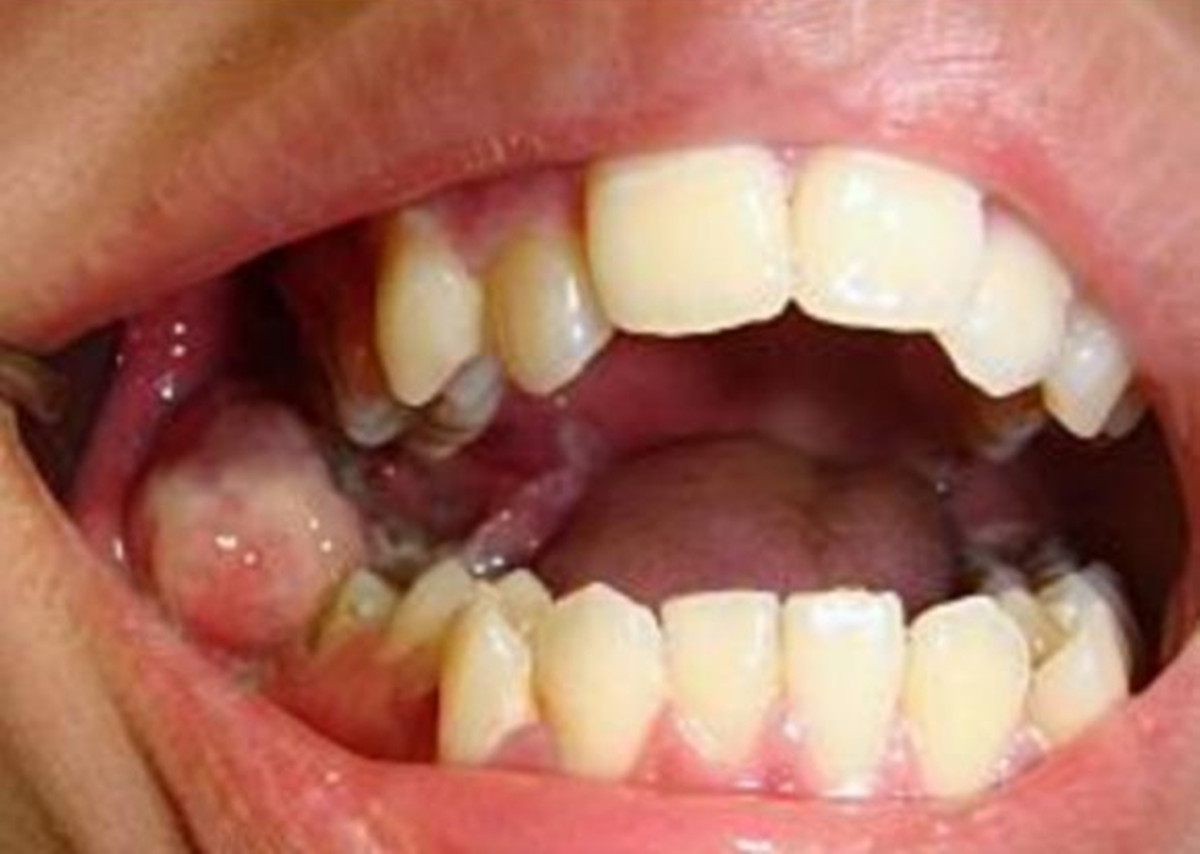

|

| Ảnh minh họa. |

Đáng nói, tế bào ung thư đã bao phủ toàn bộ xương hàm dưới bên phải, rất nguy cấp. Do bệnh nhân tuổi còn trẻ, việc trực tiếp phẫu thuật sẽ để lại sẹo rất lớn nên phải dùng phương pháp phẫu thuật đặc biệt, phức tạp hơn.